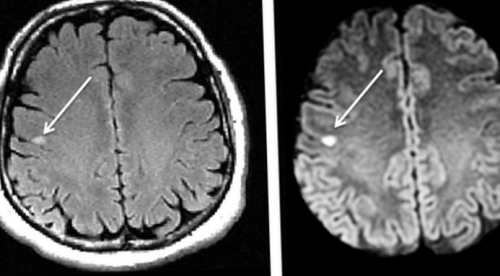

интереса;• в процессе терапии инсульт (указан стрелкой)

• выполняют сканирование зоны • после операции;DWI (слева) и FLAIR (справа) визуализируется лакунарный ишемический • Систематические физические упражнения

На МР-снимках в последовательностях